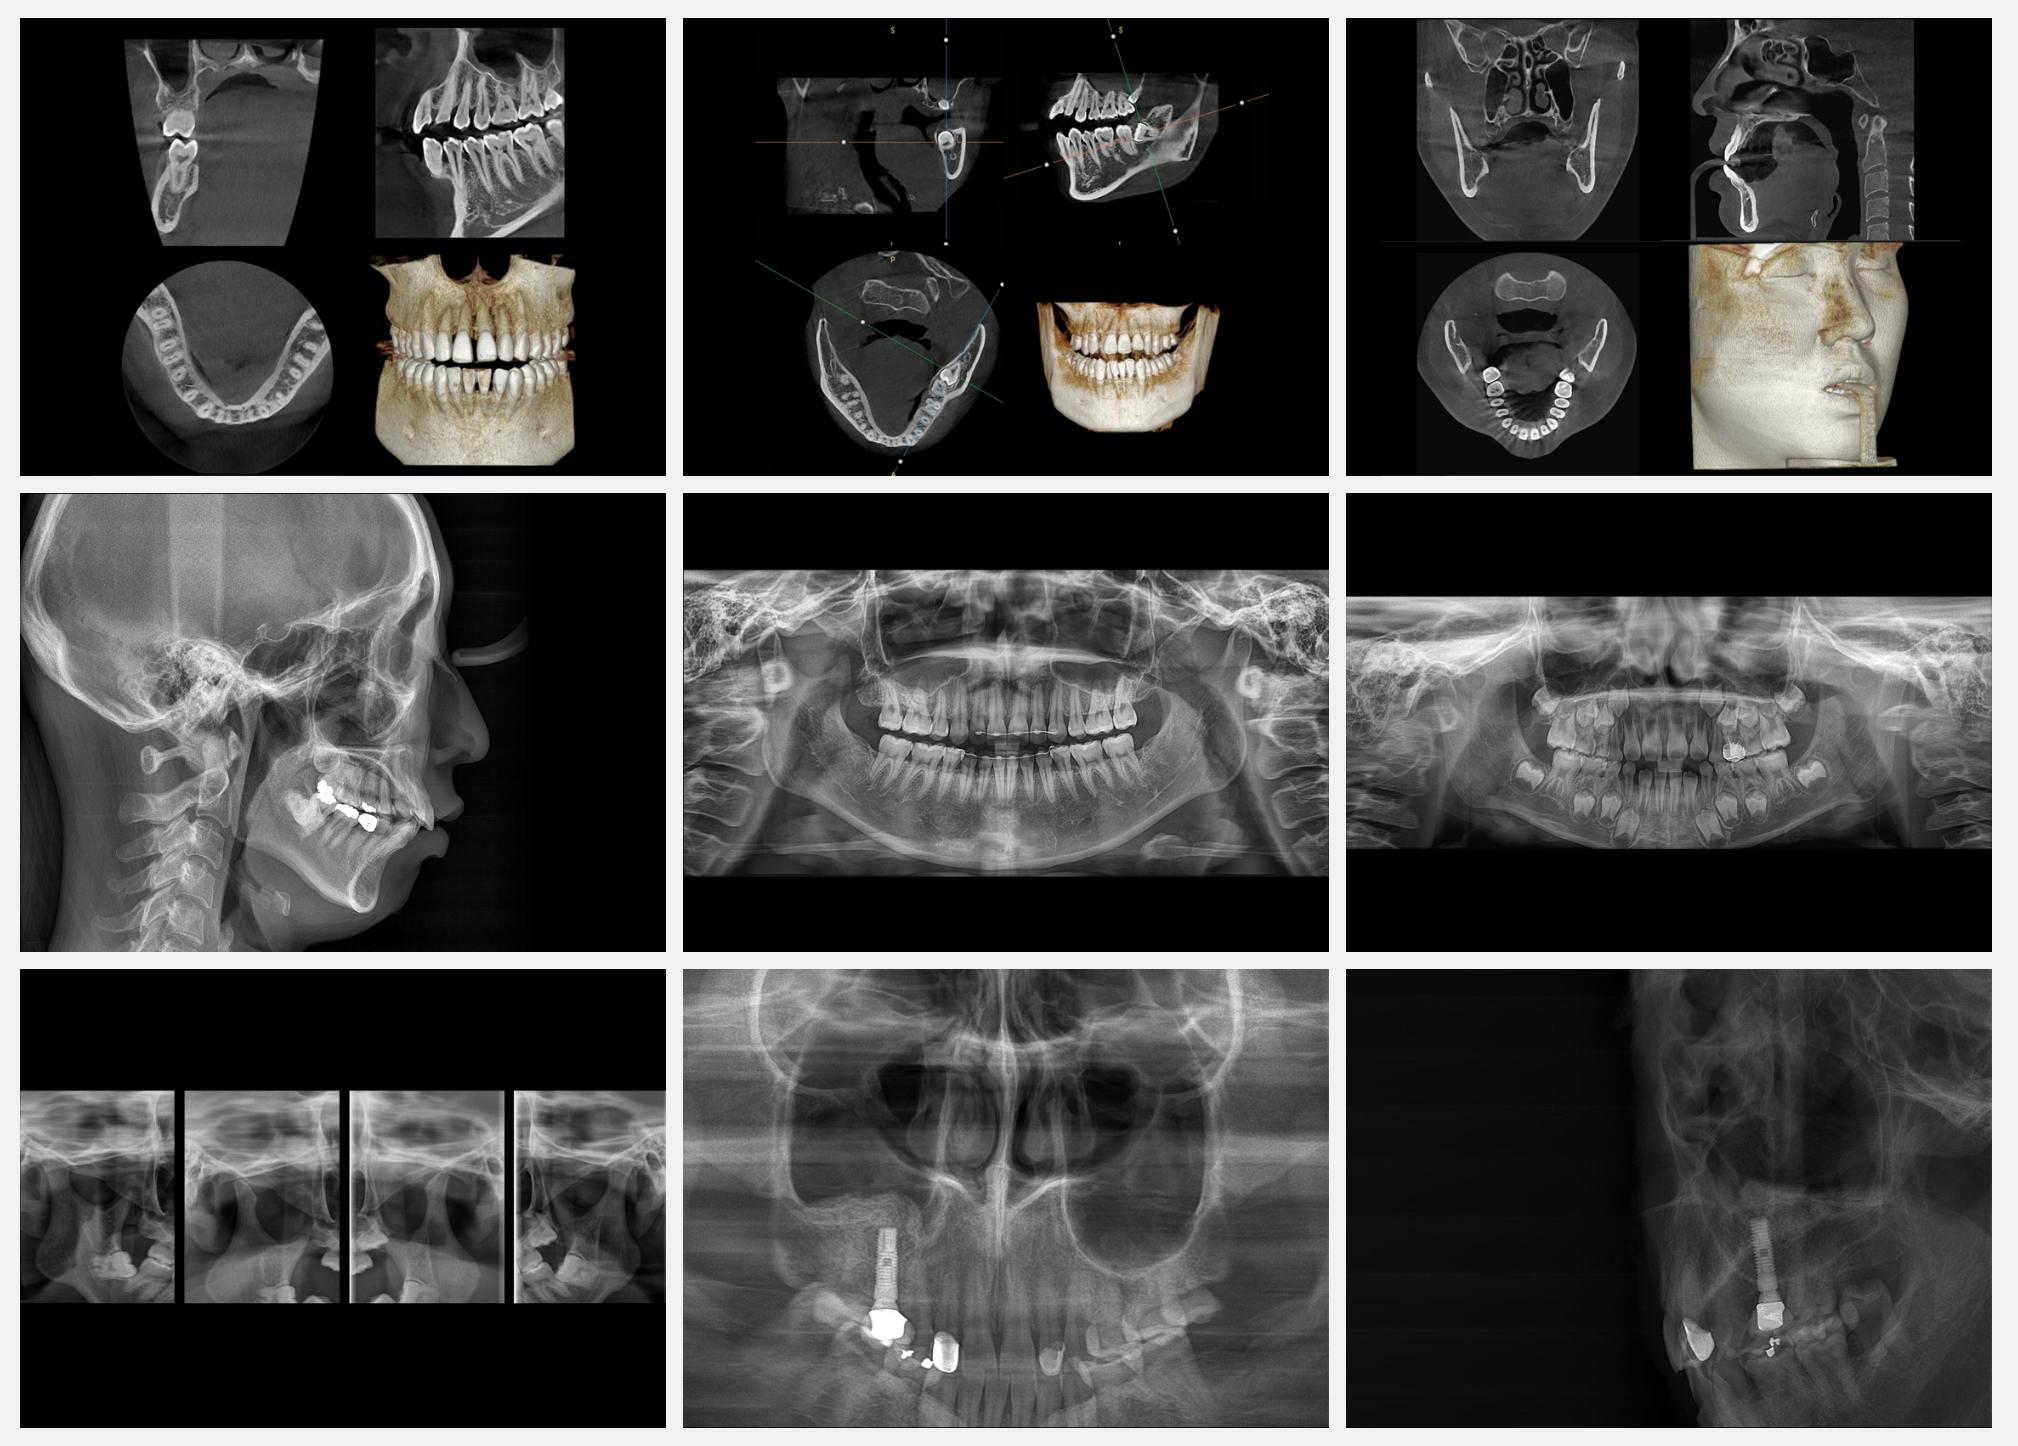

Реальні КТ-дослідження

Сучасне програмне забезпечення «Theia»

Зручне в користуванні програмне забезпечення з інтуїтивним інтерфейсом дозволяє працювати з 3D зображеннями в режимі реального часу